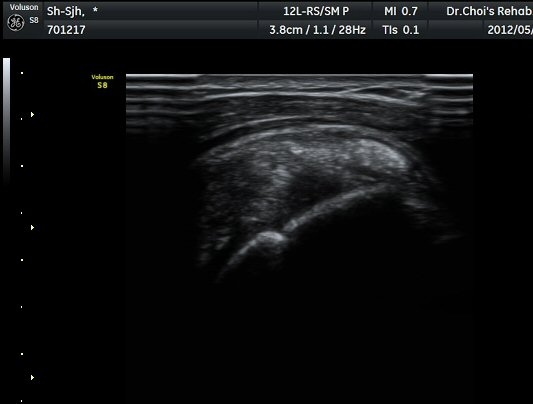

°Ë»ç¿¡¼­ Ç÷·ùÁõ°¡°¡ °üÂûµÈ´Ù(»çÁø 2). À̵ιڱ٠Á¾´Ü¸é°Ë»ç¿¡¼­µµ °Ç ÁÖÀ§ ¼ö¾×Àú·ù°¡ È®ÀÎ

µÈ´Ù(»çÁø 3). ±Ø»ó°Ç Á¾´Ü¸é°Ë»ç»ó ±Ø»ó°Ç ºÎÂøºÎ¿¡ °í¿¡ÄÚ µ¢¾î¸®°¡ °üÂûµÇ°í(»çÁø 4, 5)